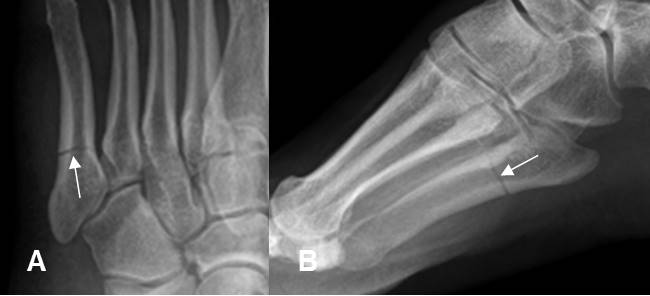

Fig 191. Fractura de Jones.

A: Rx Oblicua y B: Rx lateral. Fractura transversa, lineal y no desplazada, en el tercio proximal del 5º metatarsiano.